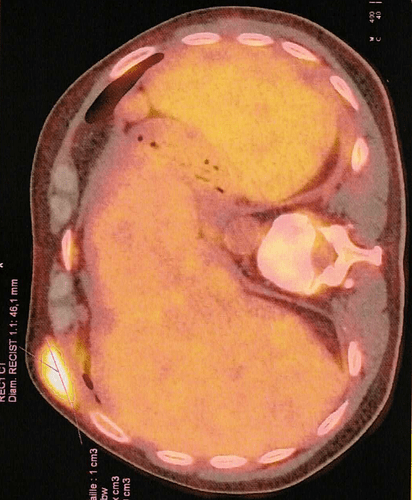

Voici quelques images du TEP Scan:

Plus c’est jaune, plus il y a de cellules cancéreuses qui se régalent en consommant le sucre radio-actif, on voit cette boule jaune au dessus de côtes, mais j’en avais une bonne dizaine à l’intérieur du corps. C’était la zone la plus hyper-métabolique de mon TEP Scan, une boule de 5 cm indolore qui avait poussé en quelques semaines. Mais on voit qu’il y en a aussi dans la rate et le foie …